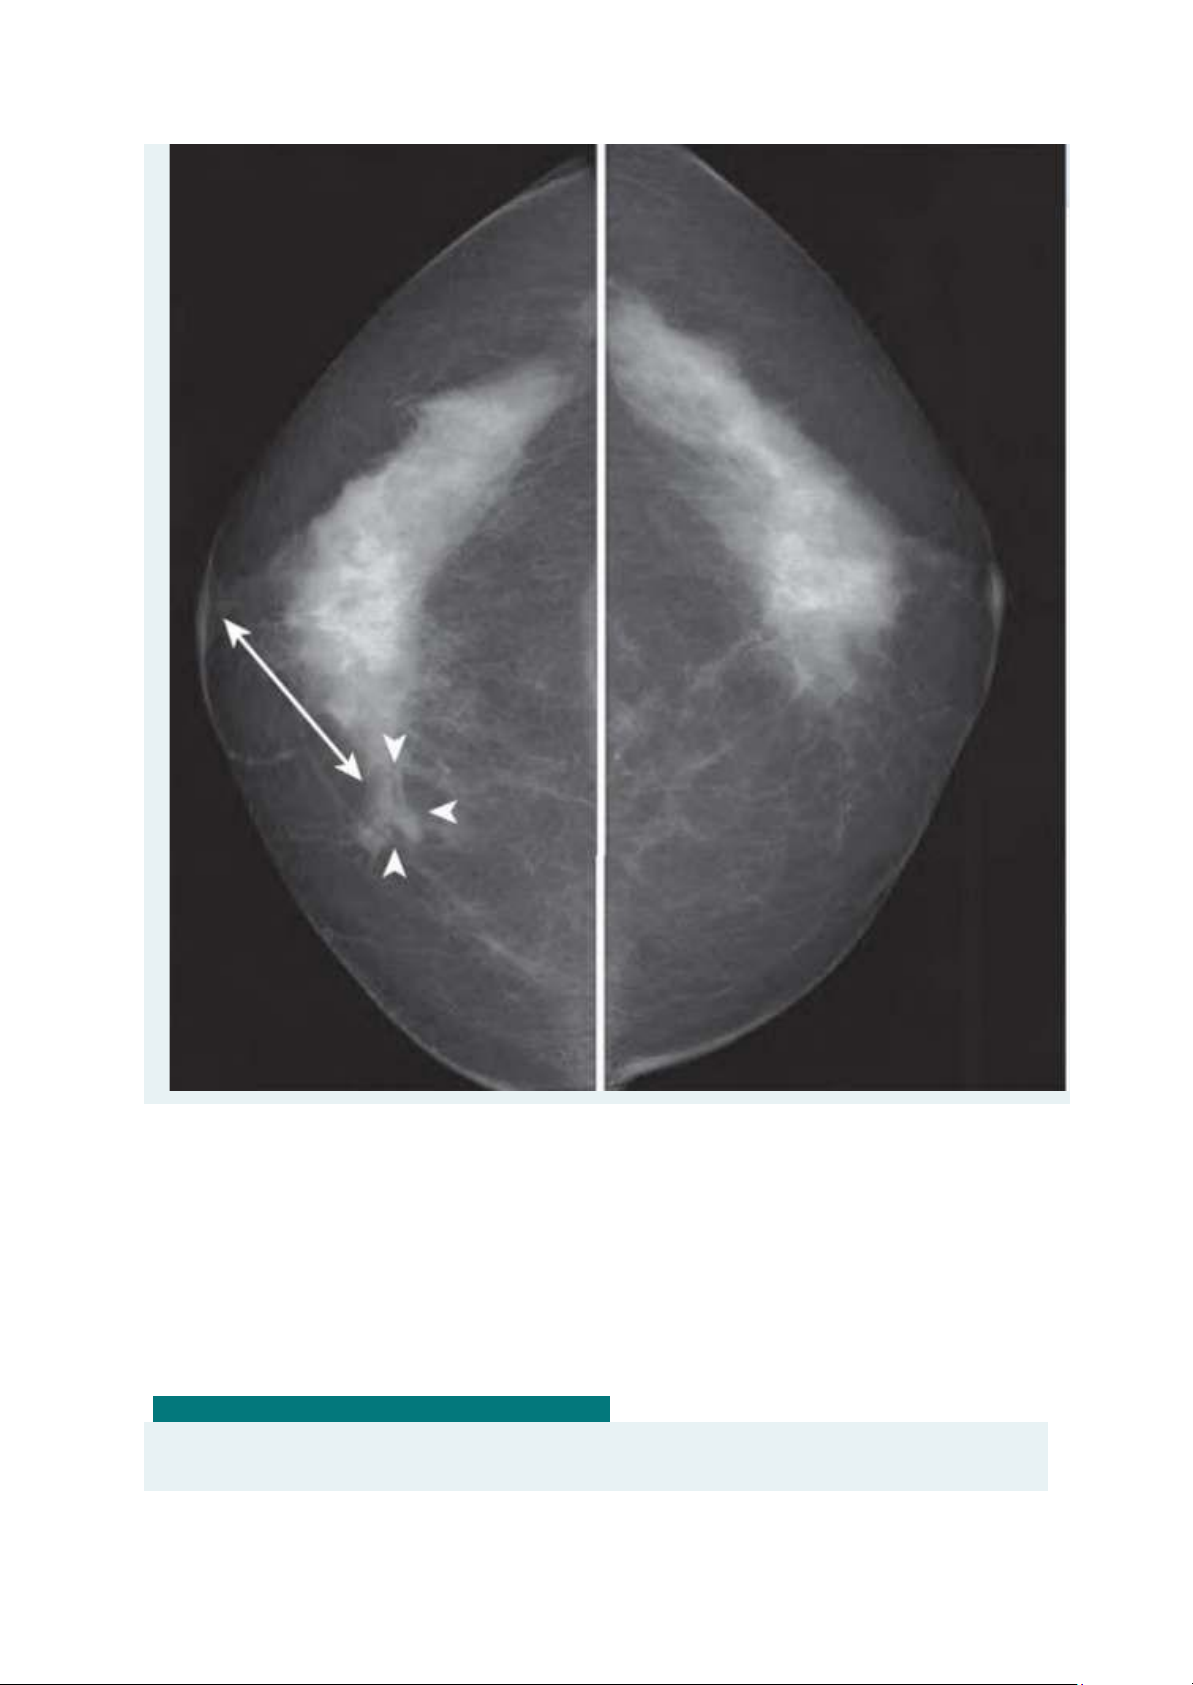

Em hãy cho biết tên tư thế của phim chụp NHŨ ẢNH này?(1 Điểm) lOMoAR cPSD| 45470709 Chếch Trong - Ngoài (MLO) Đầu - Đuôi (CC) Trong - Ngoài (ML) Chếch Ngoài - Trong (LMO) 52